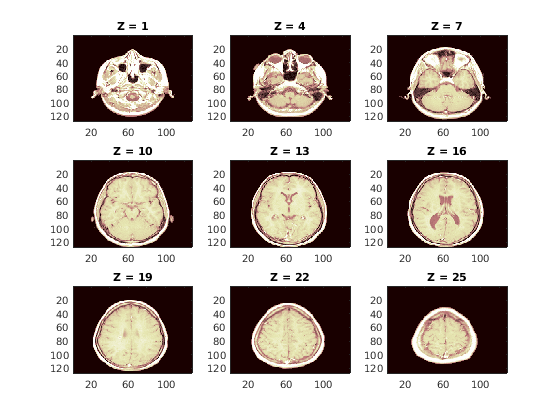

Загрузите 3-D wmri набор данных. Данные состоят из 27 128 128 изображения магнитного резонанса (MRI), расположенные в 128 128 27 массивами.

load wmriОтобразите некоторые срезы вдоль Z-ориентации исходного набора данных.

map = pink(90); idxImages = 1:3:size(X,3); figure("DefaultAxesXTick",[],"DefaultAxesYTick",[],... "DefaultAxesFontSize",8,"Color","w") colormap(map) for k = 1:9 j = idxImages(k); subplot(3,3,k) image(X(:,:,j)) str = sprintf("Z = %d",j); title(str) end